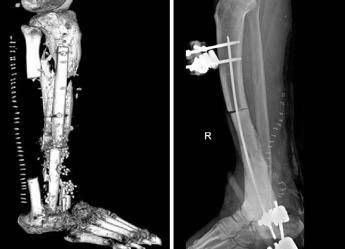

Inizialmente è stato fatto un tentativo di allungamento dell’arto con un fissatore esterno. “Si tratta di un intervento particolare – descrive l’ortopedico – consistente nell’osteotomia della parte di tibia rimanente e nella distrazione dei 2 monconi ossei (il gap osseo era di circa 20 cm), per permettere all’osso neoformato di crescere tra le porzioni di osso residue. In questo modo abbiamo recuperato 10 centimetri di osso; tanti, ma non sufficienti a ricostruire la parte mancante di tibia”.

Illustra Pataia, docente di Chirurgia ortoplastica in Cattolica e chirurgo plastico nella Uoc di Ortopedia e Traumatologia del Gemelli: “Abbiamo effettuato una ricostruzione complessa prelevando 3 lembi, un muscolo-cutaneo dalla coscia e 2 ossei da entrambi i peroni del paziente. Successivamente, questa sorta di patchwork osseo-muscolo-cutaneo è stato collegato con tecnica microchirurgica. Si tratta di un sistema detto ‘lembo-chimera’, che consiste nel collegare un lembo muscolo-cutaneo al vaso arterioso della gamba ricevente, per poi collegare tra di loro i restanti lembi. In pratica il primo lembo alimenta l’altro, attraverso una serie di connessioni vascolari realizzate al microscopio, che partendo da un solo vaso ha consentito di alimentare 3 lembi diversi”. Utilizzando infine il perone della gamba sana e quello della gamba malata, Perisano ha ricostruito la parte mancante della tibia e l’astragalo del paziente, fissando il tutto con delle viti ortopediche e mettendo a protezione un fissatore esterno circolare, per permettere la guarigione dei tessuti e far consolidare le parti ossee.